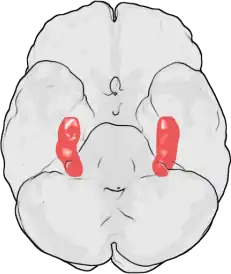

Hipocampo é uma estrutura localizada nos lobos temporais do cérebro humano, considerada a principal sede da memória e importante componente do sistema límbico. Além disso é relacionado com a navegação espacial.[1]

Seu nome deriva de seu formato curvado apresentado em secções coronais do cérebro, se assemelhando a um cavalo-marinho (Grego: hippos = cavalo, kampos = monstro marinho).[1][2]